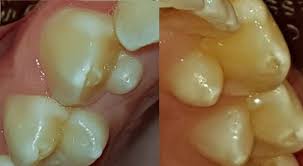

Toter Zahn Zahn Wird Schwarz Oder Verfarbt Sich Gzfa